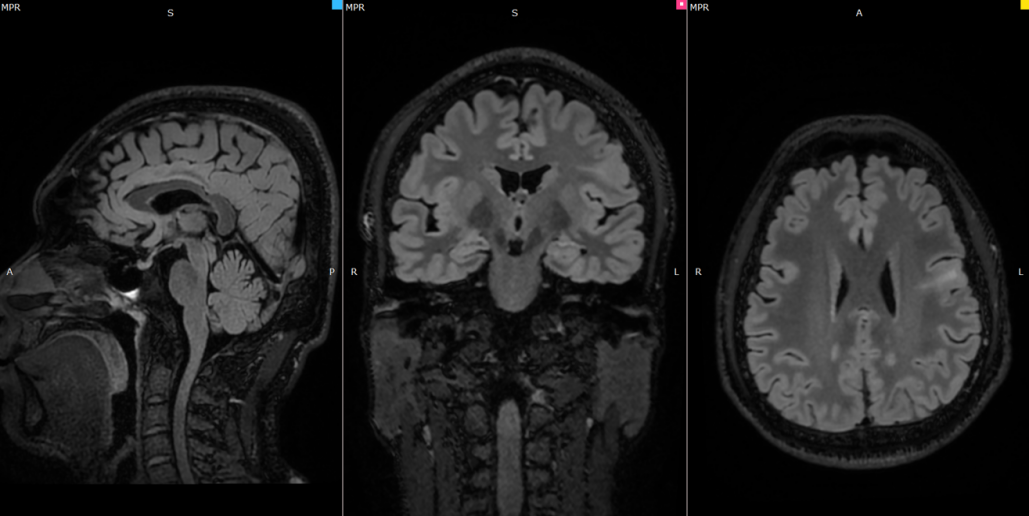

手术团队依托神经外科精准诊疗技术平台,采用神经外科手术机器人辅助定位技术,术中严格遵循微创操作规范,成功将ANS系统的深部电极、皮层电极及刺激器精准植入预设靶点。为确保手术安全与效果,术中同步开展深部及皮层脑电监测,实时捕捉DL1-DL4、SR5-SR8八导联的脑电信号,为电极定位与系统调试提供关键依据。

在ANS系统功能测试阶段,手术团队完成多次刺激启动测试,通过单极导联模式验证刺激信号传输稳定性,监测数据显示各通道刺激响应及时、波形正常,系统可精准实现“信号采集 - 分析 - 刺激”的闭环联动。术后初步评估显示,患者生命体征平稳,无手术相关并发症,植入装置工作正常,已顺利脱离麻醉恢复意识,目前正在神经外科病房接受进一步观察与术后护理。